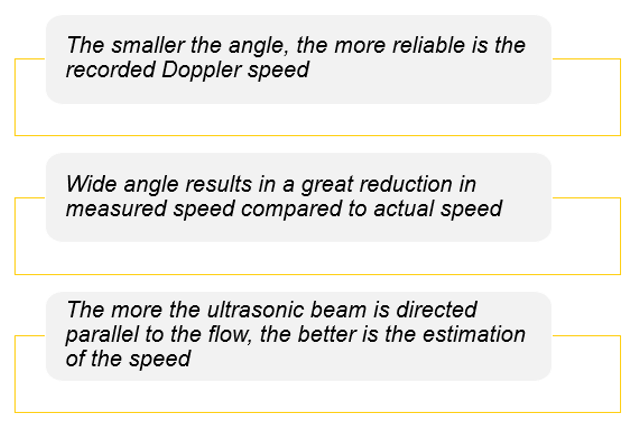

For a constant flow velocity (V), the maximum value of cosα and therefore the highest value of the Doppler-shifted signal (δf) is at an angle of 0°. This corresponds to a Doppler beam which is parallel with the vessel, which can rarely be achieved in practice.

Theoretically, when α = 90° this means the blood flow is perpendicular to the Doppler beam, cosα = 0 and no Doppler-shifted signals will register.

In practice, when measuring the blood flow, a Doppler beam angle between 30 and 60° ensures reliable Doppler-shifted signals. Avoid using angles greater than 60 degrees and remember no Doppler-shifted signals are generated at 90 degrees. The smaller the angle, the more reliable is the recorded Doppler speed.